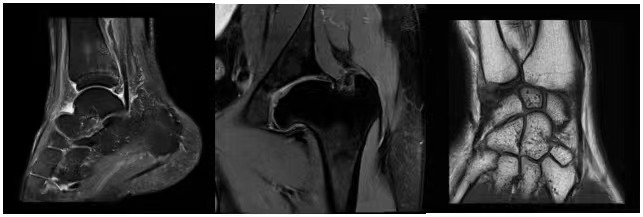

Turbo炫速成像平台

MAGNETOM Vida上配置了目前磁共振中最先进、智慧Turbo炫速成像平台。整个平台融合了近10种磁共振加速技术(包含压缩感知技术)、临床扫描策略、BioMatrix生命感知以及最新人工智能技术,从而满足不同客户的不同临床及科研加速的需求。

MAGNETOM Vida所配置超快速成像平台是目前所有3.0T磁共振中,加速采集技术最全,扫描速度最快,图像质量最好快速成像平台。